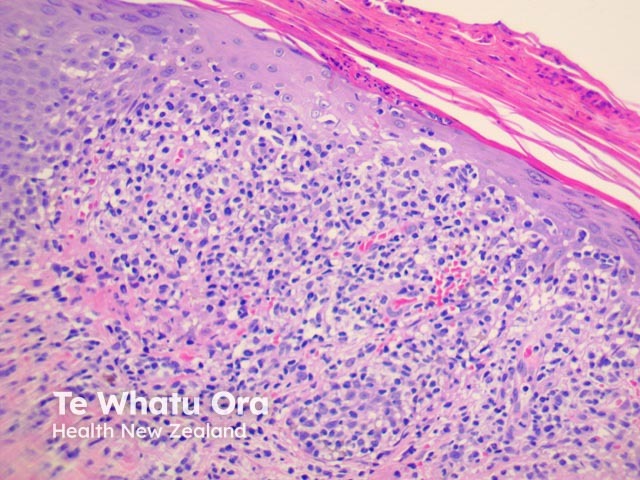

PLEVA has sharply delimited, moderately dense, lymphocytic infiltrate involving the superficial vascular plexus, which extends in a wedge-shaped pattern to involve the lower dermis (figure 1). The superficial dermis shows a dense lichenoid infiltrate and impressive exocytosis of lymphocytes into the epidermis. The overlying stratum corneum shows parakeratosis which may be confluent and contain collections of neutrophils (figure 2). The epidermis shows pronounced hydropic change and foci of keratinocyte necrosis. Scattered extravasated erythrocytes are seen (figure 3).

Figure 2